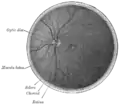

Interior of posterior half of bulb of left eye. The veins are darker in appearance than the arteries.